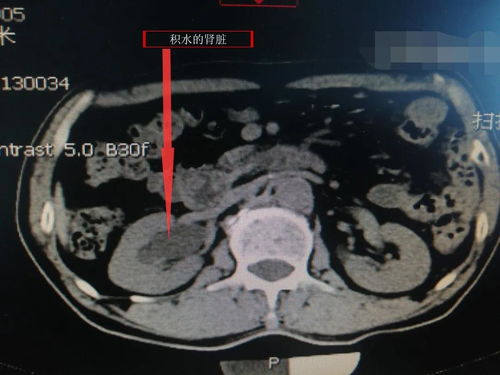

肿瘤分为良性和恶性,良性肿瘤一般形态规则,边界清晰,生长缓慢。如体积较小且无明显症状,医生可能会建议暂时观察,定期进行检查。恶性肿瘤如肺癌,其CT特征可能包括边缘毛刺、分叶状等,生长迅速,可能伴随淋巴结肿大。确诊需依靠活检。